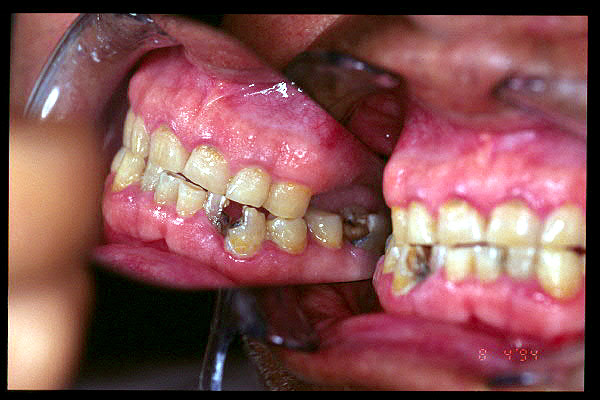

CM Caries, patología periodontal, desgaste.